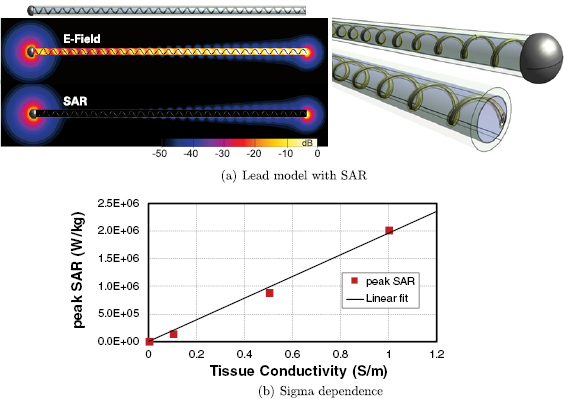

However, this mechanistic picture has been found to be incompatible with several observations made for electrically short implants, such as abandoned leads. The mechanism predicts that (i) the total deposited power should not be strongly dependent on the electrical conductivity of the tissue at the lead tip, while a nearly linear dependence is in fact observed (figure 1). Furthermore, (ii) when one of the implant ends is insulated, a dramatic reduction of the power deposition is observed (by more than two orders of magnitude for a straight, partially insulated wire; see figure 2). While insulating one end is expected to alter the antenna-like pick-up, the magnitude of the observed effect is surprising. Thus, an alternative mechanistic model for electrically small implants is needed.

Figure 1. (a) Generic model and specific absorption rate (SAR) distribution of an abandoned neuro-stimulator lead which features a helical wire structure embedded in insulating material around an air-filled core. One end consists of a large electrode, the other is the cut lead with a small cross-section of the wire exposed. (b) Tissue conductivity dependence of the peak spatial-average SAR (psSAR) at a realistic incident field strength of 150 V m−1 (64 MHz).